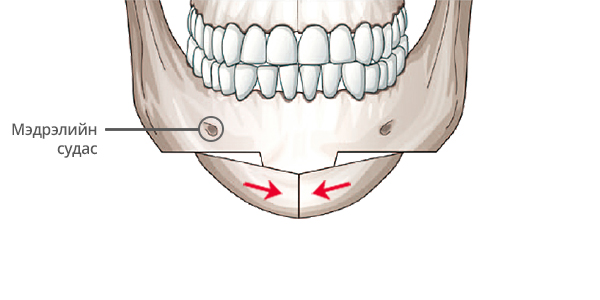

Step 4

Зүсэлт хийгдсэн эрүүг хоср талаас нь хумиж нийлүүлнэ.